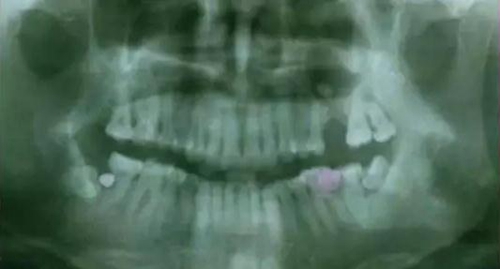

下面看一個病例,患者,女,30歲,因左下頜智齒嵌塞食物后疼痛,至當(dāng)?shù)匮揽平o予拔除,但術(shù)后1個半月,患者自覺拔牙區(qū)一直隱隱疼痛,時輕時重,遂來診。檢查發(fā)現(xiàn),拔牙創(chuàng)口一直未愈合,未見明顯腫脹,拍片發(fā)現(xiàn),拔牙窩內(nèi)顯示高密度斷根影

像,該斷根臨近下頜神經(jīng)管,同時發(fā)現(xiàn)第二磨牙遠中有兩塊高密度影像,疑似殘留骨片或牙片,應(yīng)該是引起疼痛的原因,經(jīng)與患者溝通,采納建議,進行二次拔牙。

下邊也是一個斷根病例